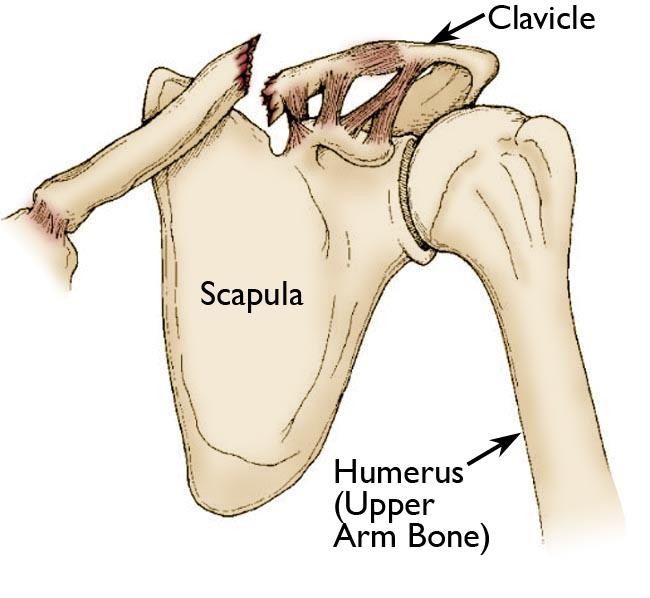

Shoulder Anatomy

The clavicle is located between:

- The sternum (breastbone)

- The scapula (shoulder blade)

It acts as a strut that holds the shoulder away from the chest and allows free arm movement.